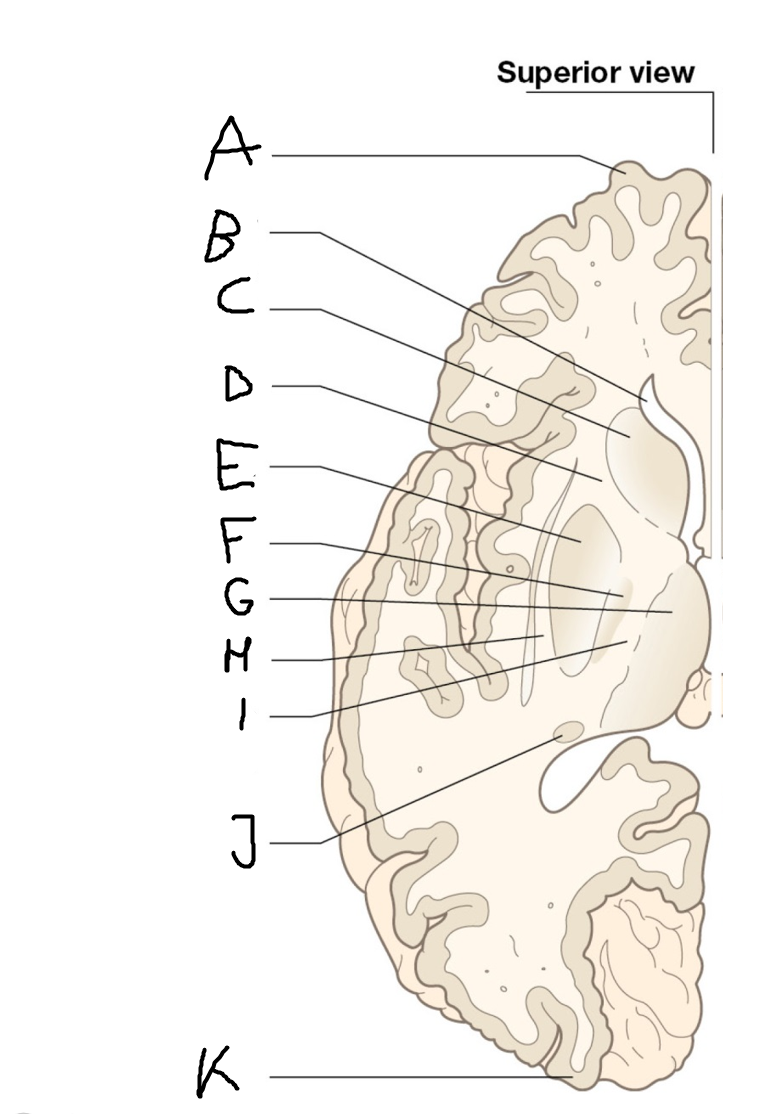

caudate nucleus head

A

Putamen

B

caudate nucleus tail

C

Lateral ventricle

D

caudate nucleus body

E

internal capsule

F

A

corpus callosum

B

cerebral cortex

C

caudate

D

putamen

F

anterior commissure

G

amygdala

H

optic chiasm

I

basal forebrain nuclei

K